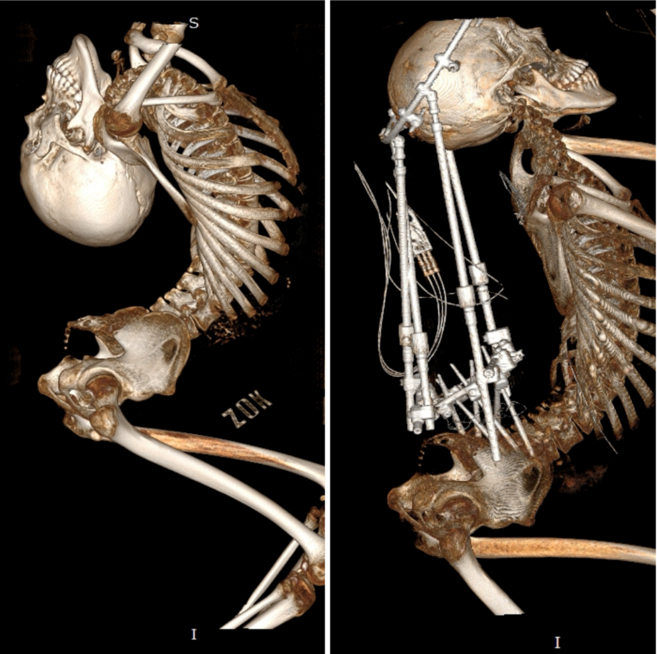

姜延琛的脊柱影像

第一次手术前后的对比

如今,他的身体

从反向折叠180度到展开90度

从反向折叠180度到矫正90度的转变